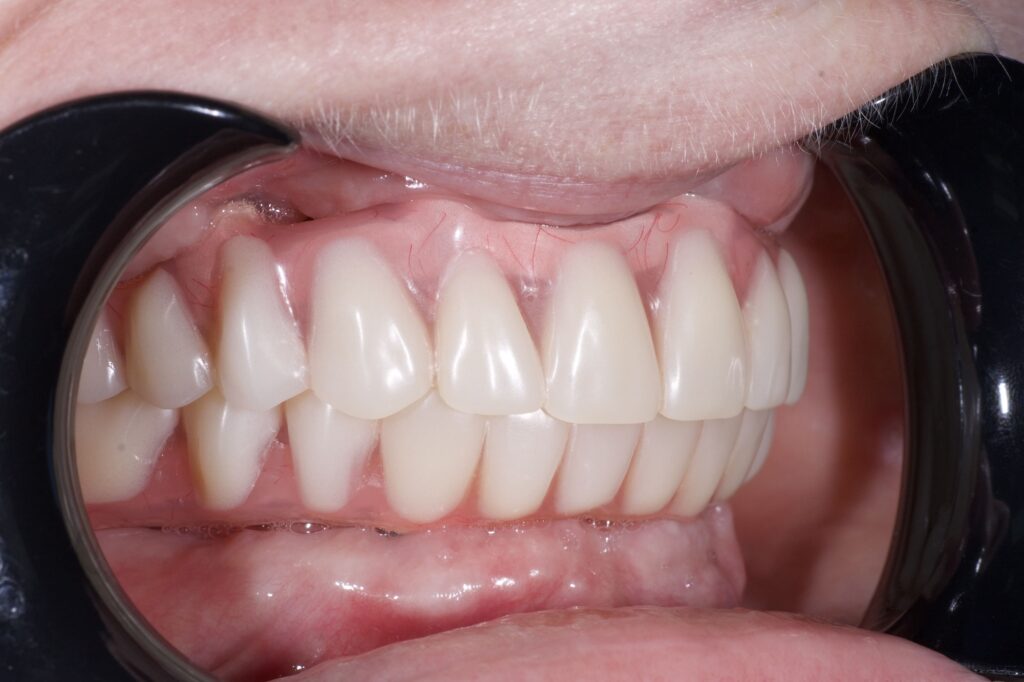

Пациент обратился к нам с целью перепротезирования на постоянные протезы (комплексная имплантация по системе All-on-6 на обе челюсти была проведена в 2024г. специалистами нашей клиники).

По прошествию года было изготовлено 2 постоянных циркониевых протеза на титановой балке.

результат протезирования